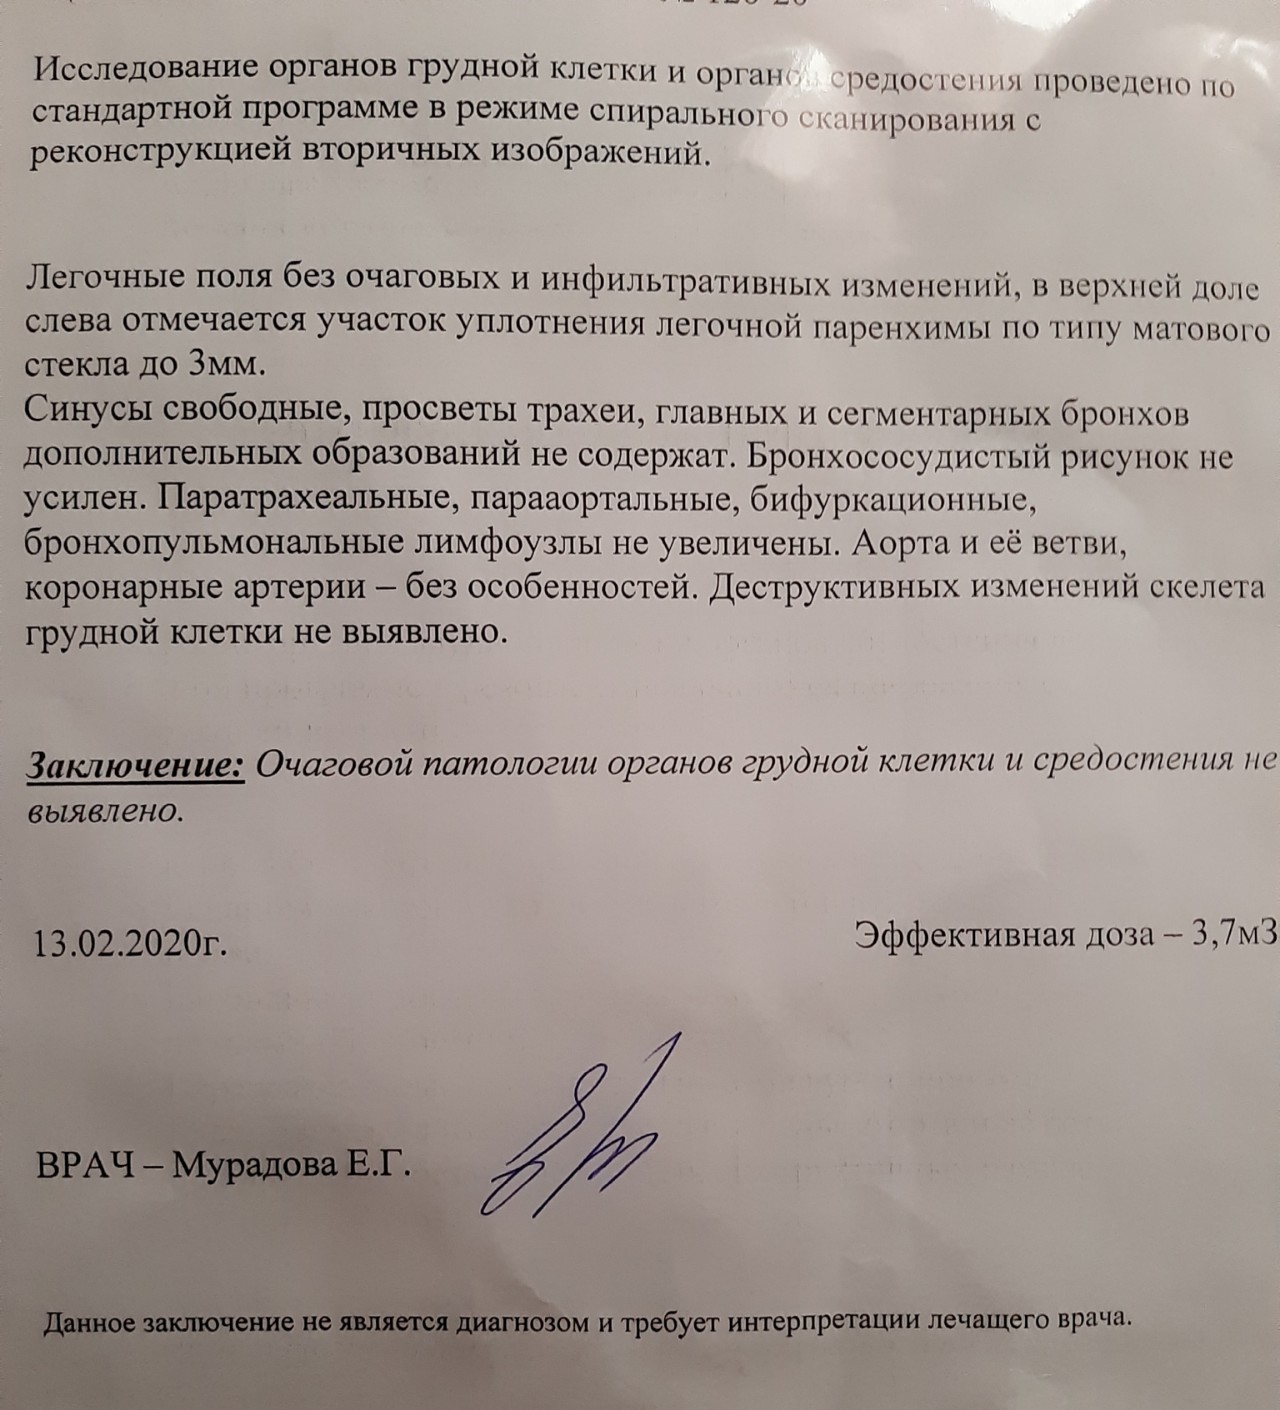

Рентгеновские и МРТ снимки легких